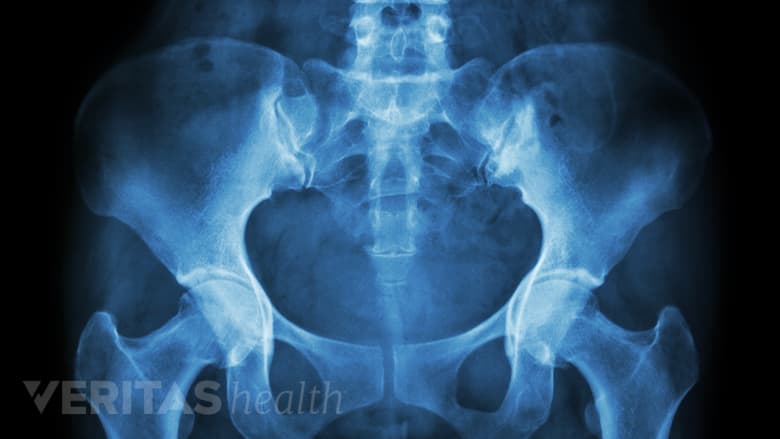

Una pelvis más ancha en las mujeres las hace más susceptibles al síndrome piriforme.

- Sexo. Las mujeres tienen hasta 6 veces más probabilidades de desarrollar el síndrome del piriforme que los hombres debido a un hueso pélvico más ancho.,